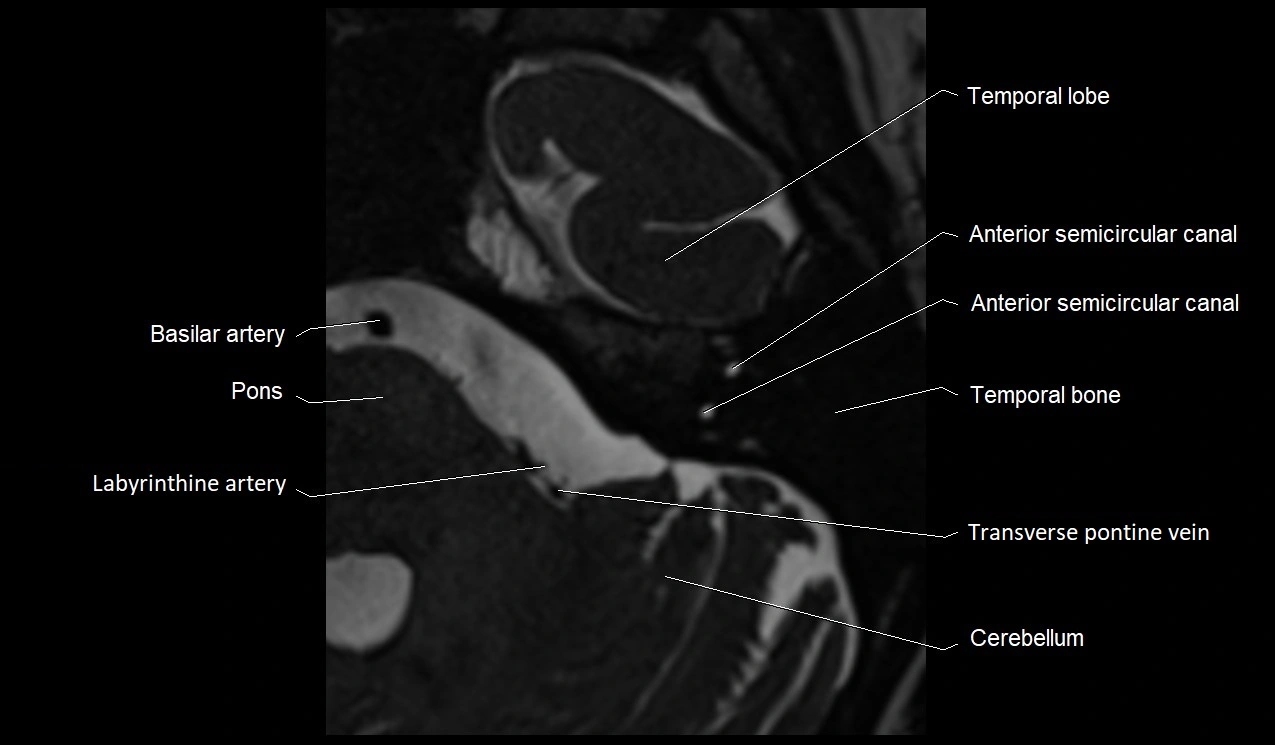

MRI Appearance

• The abducens nerve is a small, thin, linear structure

• Best visualized on high-resolution T2-weighted 3D MRI sequences (e.g., FIESTA or CISS)

• Seen as a hypointense (dark) line running from the brainstem at the pontomedullary junction, traversing the prepontine cistern, and entering Dorello’s canal under the petrosphenoidal ligament, then into the cavernous sinus, and finally the orbit

• May be challenging to visualize in standard MRI due to its small size

• Pathology may be inferred by absence, displacement, or enhancement of the nerve